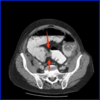

Colonoscopy/OGD, barium enema, CT pneumocolon [Pic]

Confirm site of blockage via CT/gastrograffin enema [Pic]